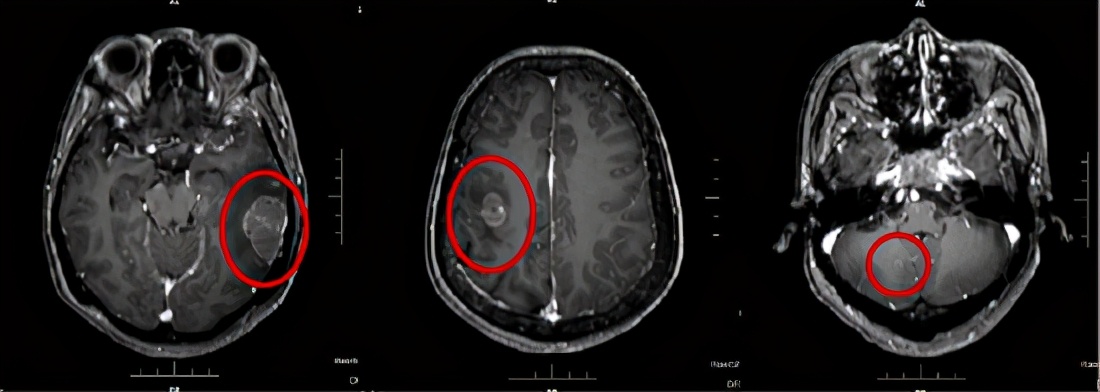

2020年8月,患者找到哈医大一院肿瘤一科主任张大昕教授,诊断为晚期肺腺癌、多发脑转移、多发淋巴结及脏器、软组织转移。

“对于同这位病患一样尝试过多线治疗、“走投无路”的患者来说,是没有公认有效的治疗方案的,甚至可以说这一类患者绝大多数都被直接宣判了‘死刑’。”面对这部分病患,张大昕主任没有放弃一丝的治疗可能,结合患者的基因检测及肿瘤微环境,制定了个性化“免疫治疗联合高低剂量放疗”的精准治疗方案,从死亡边缘挽救了患者的生命。

坚持治疗2个周期后,患者复查结果提示病情稳定无进展,这就意味着新的治疗方案有效了。在那段最难熬的日子里,医护人员经常在患者半夜无法安睡时跟她聊天,鼓励她积极应对生活。目前,患者的身体状况已趋于正常,只需定期回医院治疗并定期复查。